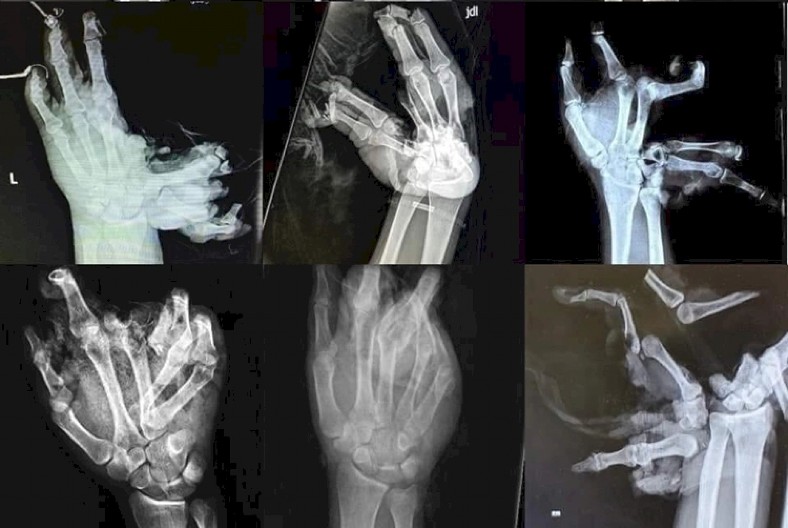

Dečak je primljen u Univerzitetsku dečiju klinku u Tiršovoj sa teškom povredom ruke. Lekari su mu konstatovali teške povrede prstiju i zadržan je na odeljenju plastične hirurgije.

Dvojica dečaka su prethodnih dana, takođe teško povređena kad im je petarda eksplodirala u šaci.

Dečak (14) zadobio je teške povrede šake na Zvezdari i zbog ozbiljnosti povreda hitno je transportovan u Institut za majku i dete.

Tinejdžeru (15) iz Kruševca petarda je eksplodirala u ruci dok je pokušavao da je upali. On je prebačen u Klinički centar Niš. Njemu je paralelno rađena rekonstrukcije obe šake, koju su izvodili dečiji hirurg i plastični hirurg.